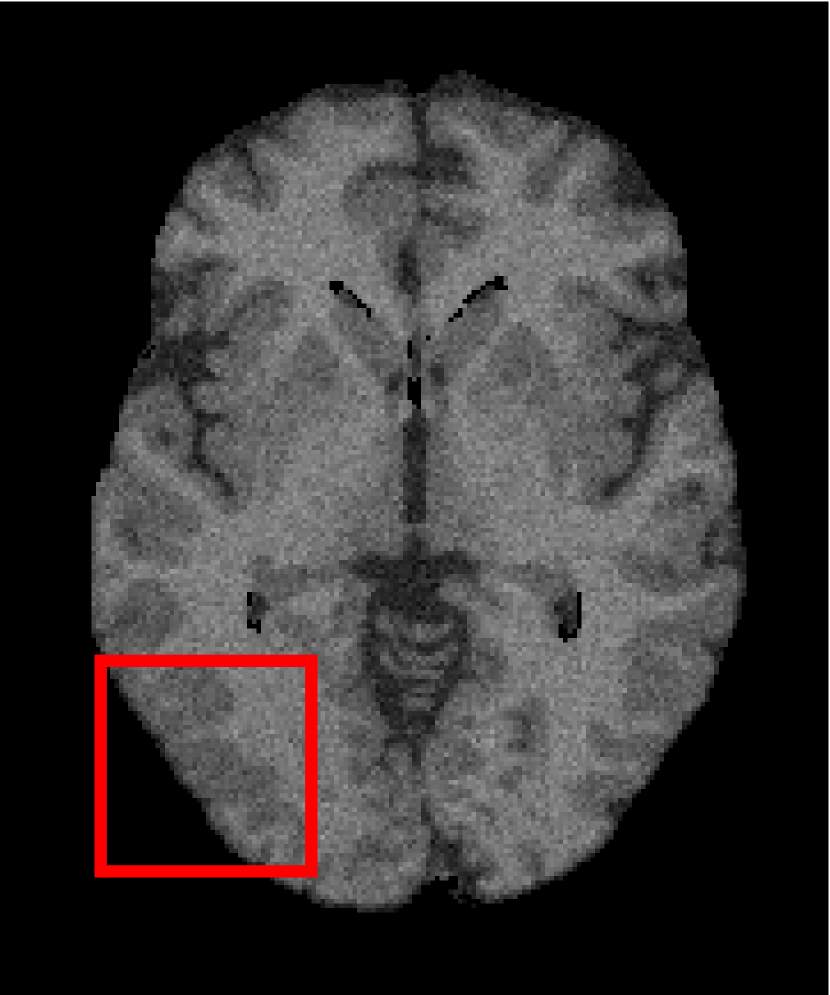

Next, we representatively segment five medical images from BrianWeb. They are represented as five slices in the axial plane with a sequence of 70, 80, 90, 100 and 110, which are generated by T1 modality with slice thickness of 1mm resolution, 9% noise and 20% intensity non-uniformity. Here, we set c=4𝑐4c=4 for all cases. The comparison between WRFCM and its peers are shown in Fig. 9 and Table II. The best values are in bold.

Figure 9: Segmentation results on five medical images. The parameter: ϕ=5.35italic-ϕ5.35\phi=5.35. From top to bottom: noisy images, ground truth, and results of FCM_S1, FCM_S2, FLICM, KWFLICM, FRFCM, WFCM, DSFCM_N, and WRFCM.

By a view of the marked red square in Fig. 9, we find that FCM_S1, FCM_S2, FLICM, KWFLICM and DSFCM_N are vulnerable to noise and intensity non-uniformity. They give rise to the change of topological shapes to some extent. Unlike them, FRFCM and WFCM achieve sufficient noise removal. However, they produce overly smooth contours. Compared with its seven peers, WRFCM can not only suppress noise adequately but also acquire accurate contours. Moreover, it yields the visual result closer to ground truth than its peers. As Table II shows, WRFCM obtains optimal SA, SDS and MCC results for all five medical images. As a conclusion, it outperforms its peers visually and quantitatively.